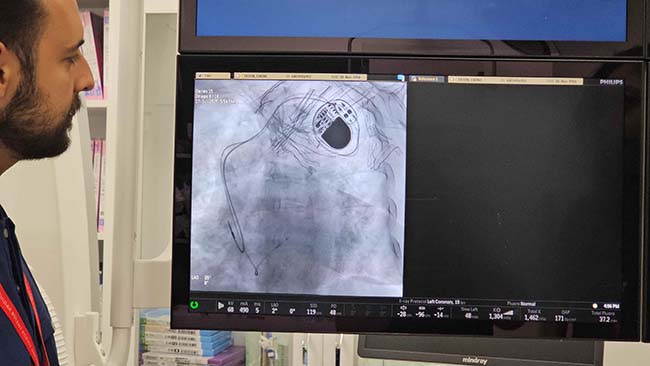

Zonguldak Bülent Ecevit Üniversitesi (BEUN) Tıp Fakültesi Kardiyoloji Ana Bilim Dalı'nda; ritim bozukluğu yaşayan hastalar için yakma (ablasyon) ve dondurma (kriyoablasyon) işlemleri uygulanmaya başlandı.

Kardiyoloji Ana Bilim Dalı Doktor Öğretim Üyesi İlke Erbay, bölgede önemli bir eksikliği giderdiklerini belirterek, "Ritim bozukluğu olan hastalarda yakma ve dondurma işlemlerini kapsayan bir yöntemdir. Bunun daha öncesinde bölgemizde kısa bir süre içerisinde de gerçekleştirilmiş olup şu anda tekrardan devamlılığını sağlayacağız" dedi.

Erbay, bölgede birçok aritmi hastasının İstanbul, Ankara ve İzmir gibi büyük merkezlere sevk edildiğini belirterek, "Bu ritim bozukluğu hastalarımızda özellikle ölümcül ritim bozukluğu olan ya da hayat kalitesini düşüren ritim bozukluğu olan hastalarımızda yakma işlemleri ve dondurma işlemlerini kurumumuzda ve bölgemize hizmeti sunmaya başladık. Zaten vakalarımıza hızlı bir şekilde başladık" ifadelerini kullandı.